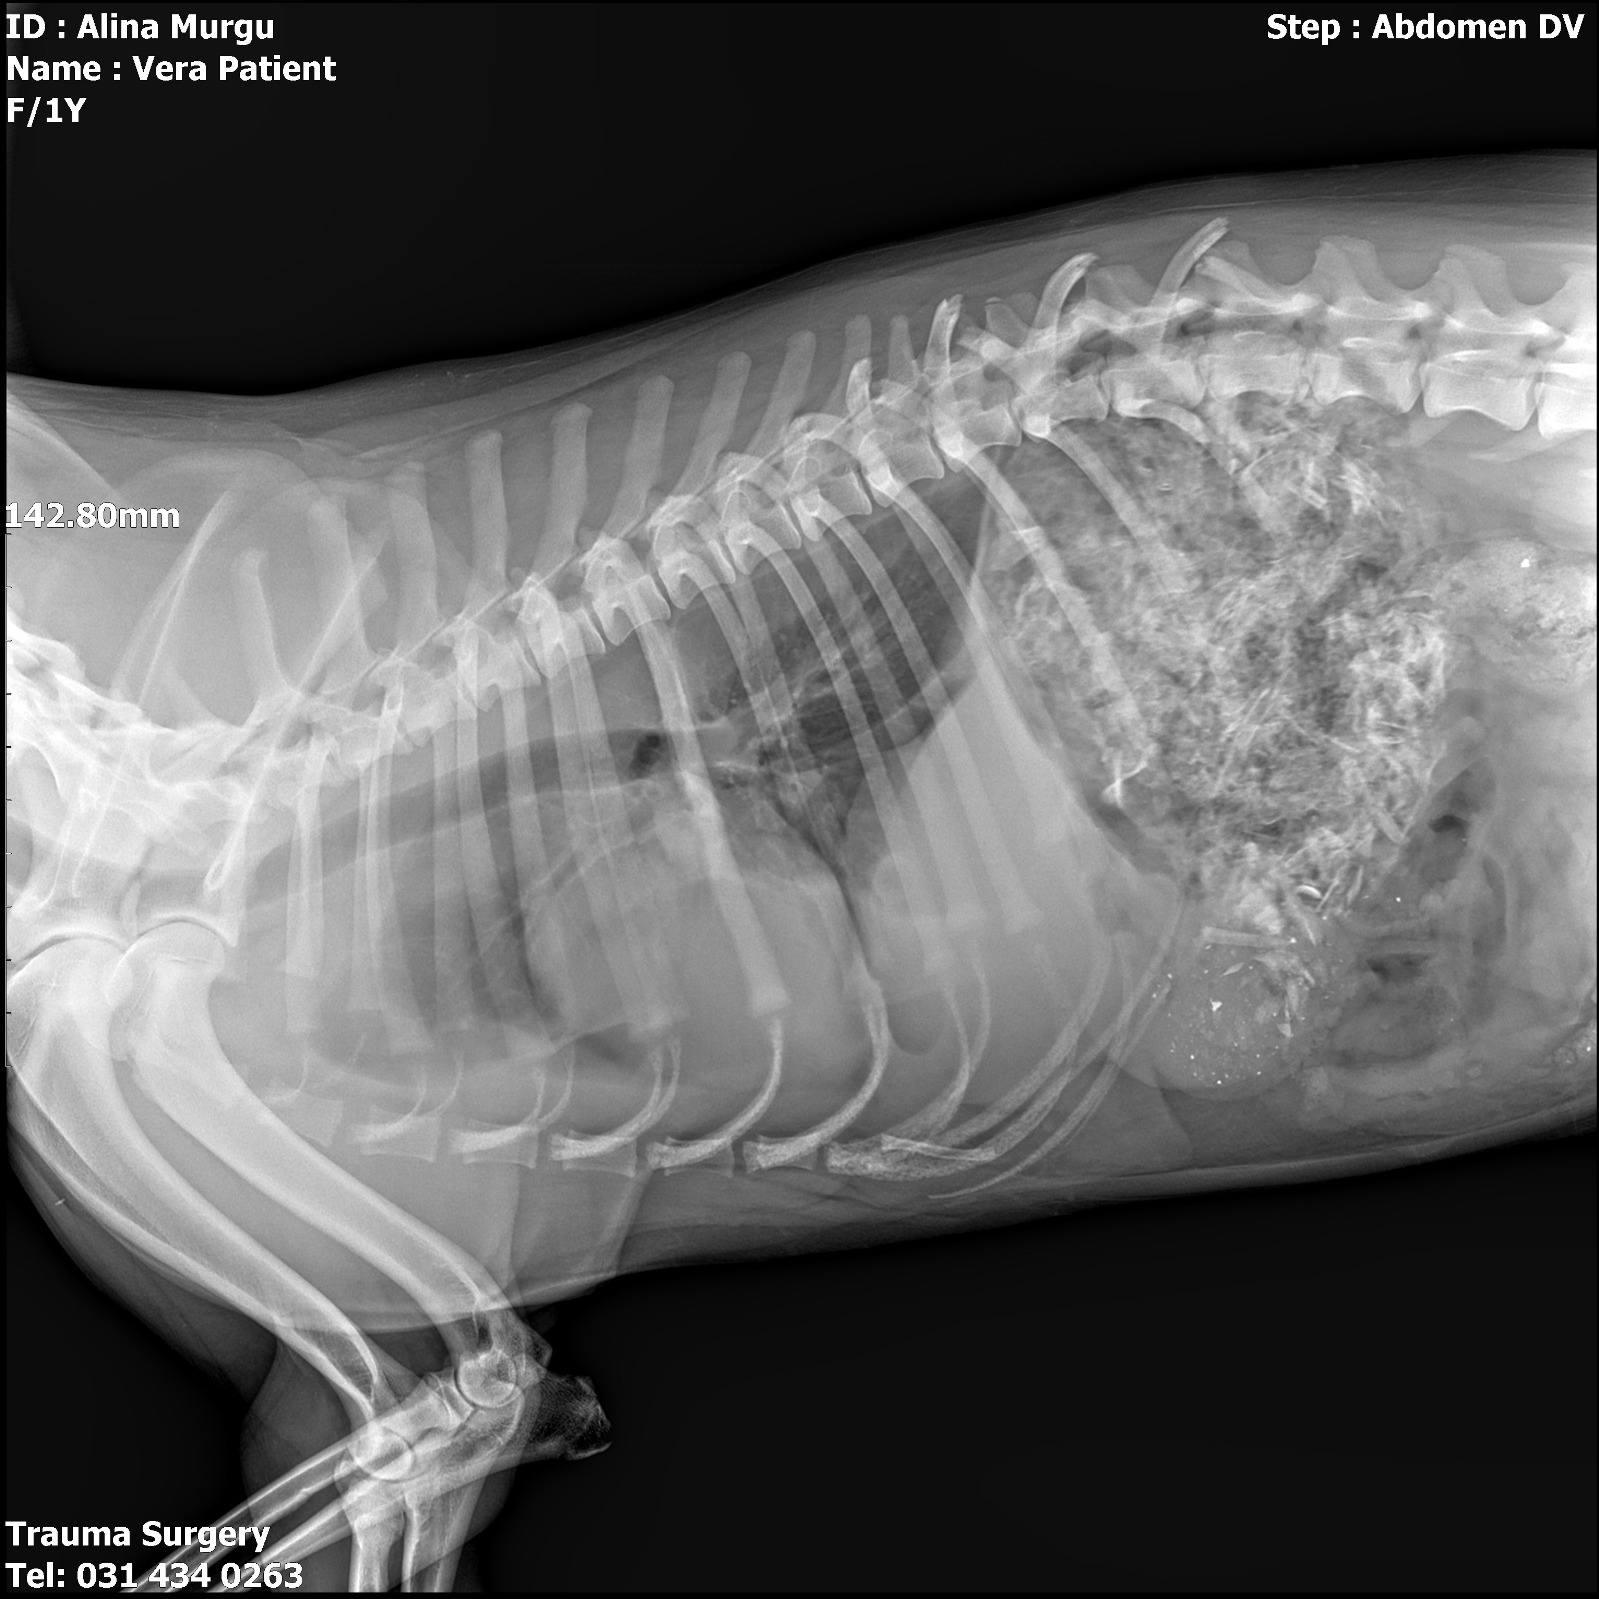

Le diagnostic est lourd : cette chienne courageuse souffre d’une fracture du bassin et a quatre côtes cassées. Face à ces blessures qui menacent sa vie et sa mobilité, le verdict des vétérinaires est sans appel : une intervention chirurgicale est nécessaire, et elle a eu lieu le jour même.